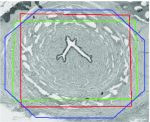

Appearance is one of the most important visual cues to distinguish between different structures in an image. Appearance is described by studying the distribution of different features such as intensity values in gray-scale images, color, and texture inside each object. In most cases, appearance models are incorporated into the data term in (2) and (7). The purpose of incorporating appearance prior is to fit the appearance distribution of the segmented objects to the distribution of objects of interest, e.g. using Gaussian mixture model (GMM) (Rother et al., 2004). In the literature, there are two ways to model the appearance: 1) adaptively learning the appearance during the segmentation procedure, and 2) knowing the appearance model prior to performing segmentation (e.g. by observing the appearance distribution of the training data). In the former case, the appearance model is learned as the segmentation is performed (Vese and Chan, 2002) (computed online). In the second case, it is assumed that the probability of each pixel belonging to particular label is known, i.e. if represents a particular set of feature values (e.g. intensity/color) associated with each image location for object, then it is assumed that is known (or pre-computed offline). This probability is usually learned and estimated from the distribution of features inside small samples of each object. Figure 9 illustrates the probability of different structures (the kidney, the tumour, and the background) in an endoscopic scene. A lower intensity in Figures 9(b-d) corresponds to higher probability.